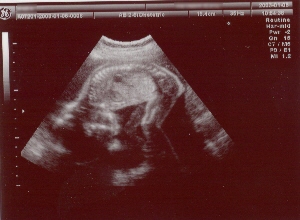

今日の胎児の写真は、いつものモノクロに加えてカラーもあります。

モノクロの写真は、頭から背骨、足までハッキリと分かります。